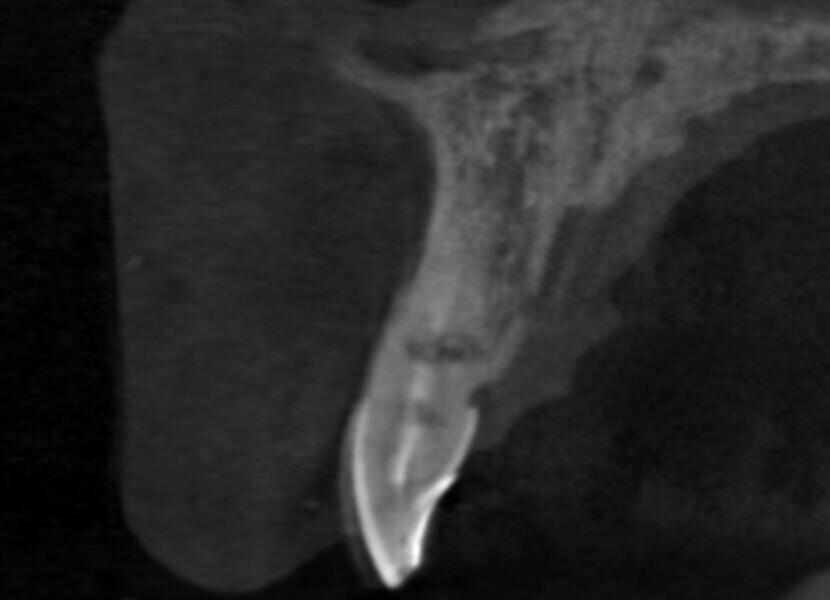

Immediate placement and restoration of a Straumann BLX implant replacing maxillary incisors